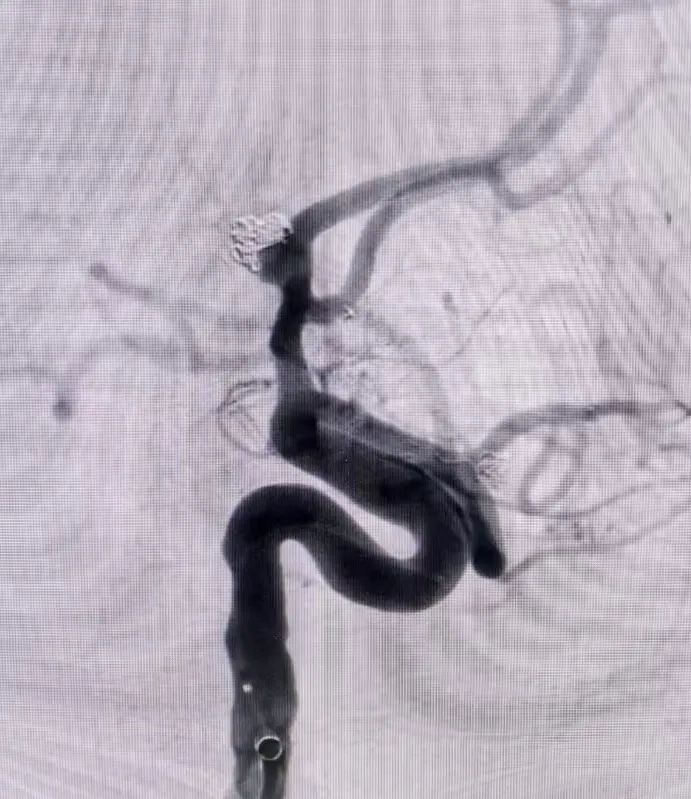

面对大动脉瘤且血管条件差的患者(腹主动脉S型迂曲,右侧颈总动脉II型牛角弓),以及颈内动脉多发动脉瘤的不同患者(C5-C7有5枚动脉瘤),吴全主任团队运用密网支架对症治疗,用一个支架巧妙解决大动脉瘤或多个动脉瘤难题,效果良好,患者短时间内快速恢复。

对于非责任动脉瘤的处理,医生们更是展现出专业与耐心。9个月前,患者动脉瘤破裂出血,当时造影发现2处动脉瘤,术中优先处理责任动脉瘤,待患者身体恢复后择期处理非责任动脉瘤。此次处理非责任动脉瘤,手术中造影,发现责任动脉瘤栓塞术后复发(3月前复查尚无),医生们当机立断,同期处理两个动脉瘤,省钱的同时,也成功为患者解除隐患。